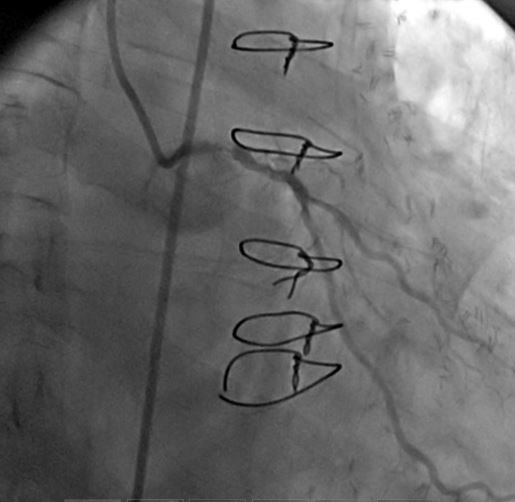

1) LM: subtotal ISR lesion (figure 2, figure 3)

A CLs guiding catheter was used to engage the left coronary artery, and a Choicd floppy guidewire passed through the lesion. The lesion was predilated with a 1.5x15mm and 2x10mm Maveric balloon (figure 4). Then a 3.5x18mm Xience v stent was deployed at 16atm (figure 5, figure 6, figure 7). Post-dilation was done with a 4x10mm Firestar NC balloon (figure 8). The final result showed TIMI-III flow with no residual stenosis (figure 9).